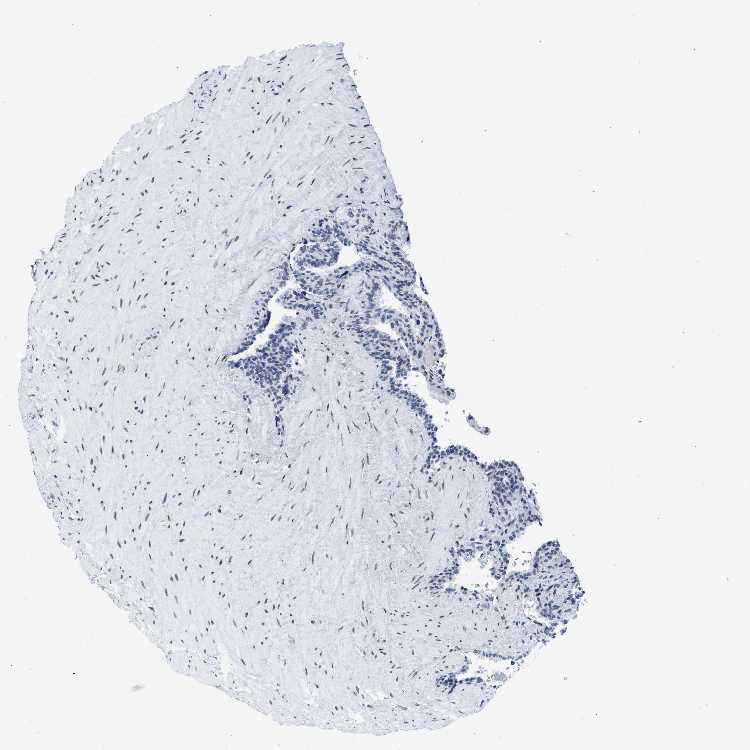

SEMINAL VESICLE - Antibody stainingi

Antibody staining in the annotated cell types in the current human tissue is reported as not detected, low, medium, or high, based on conventional immunohistochemistry profiling in selected tissues. This score is based on the combination of the staining intensity and fraction of stained cells.

Each image is clickable and will lead to virtual microscopy that enables deeper exploration of all samples and also displays staining intensity scores, fraction scores and subcellular localization as well as patient and tissue information for each sample.

Antibody HPA018987Antibody HPA044971Antibody CAB004217

Glandular cells Not detectedMediumHigh